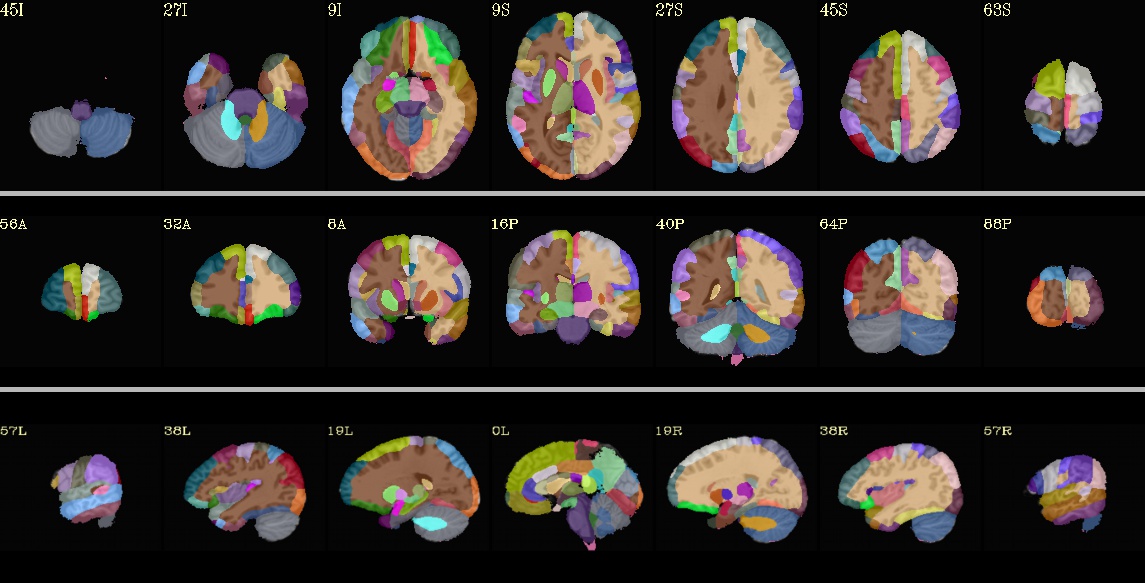

This page provides a list of the overlays (atlases, masks, and more) in the “afni_atlases_dist.tgz” package that is distributed with AFNI code. Axial and sagittal images are shown for each. The listing is in alphabetical order.

This section contains integer-valued datasets. This includes popular whole-brain atlases, hemisphere-masks, and various subsets of regions.